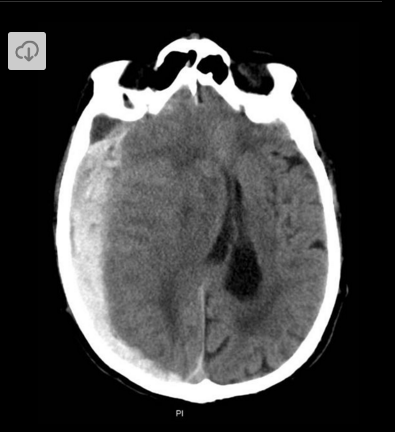

A man presents to hospital after falling off his bike. This is his CT scan, what is the diagnosis?

Acute subdural haemmorhage (Distinctive crescent shape)